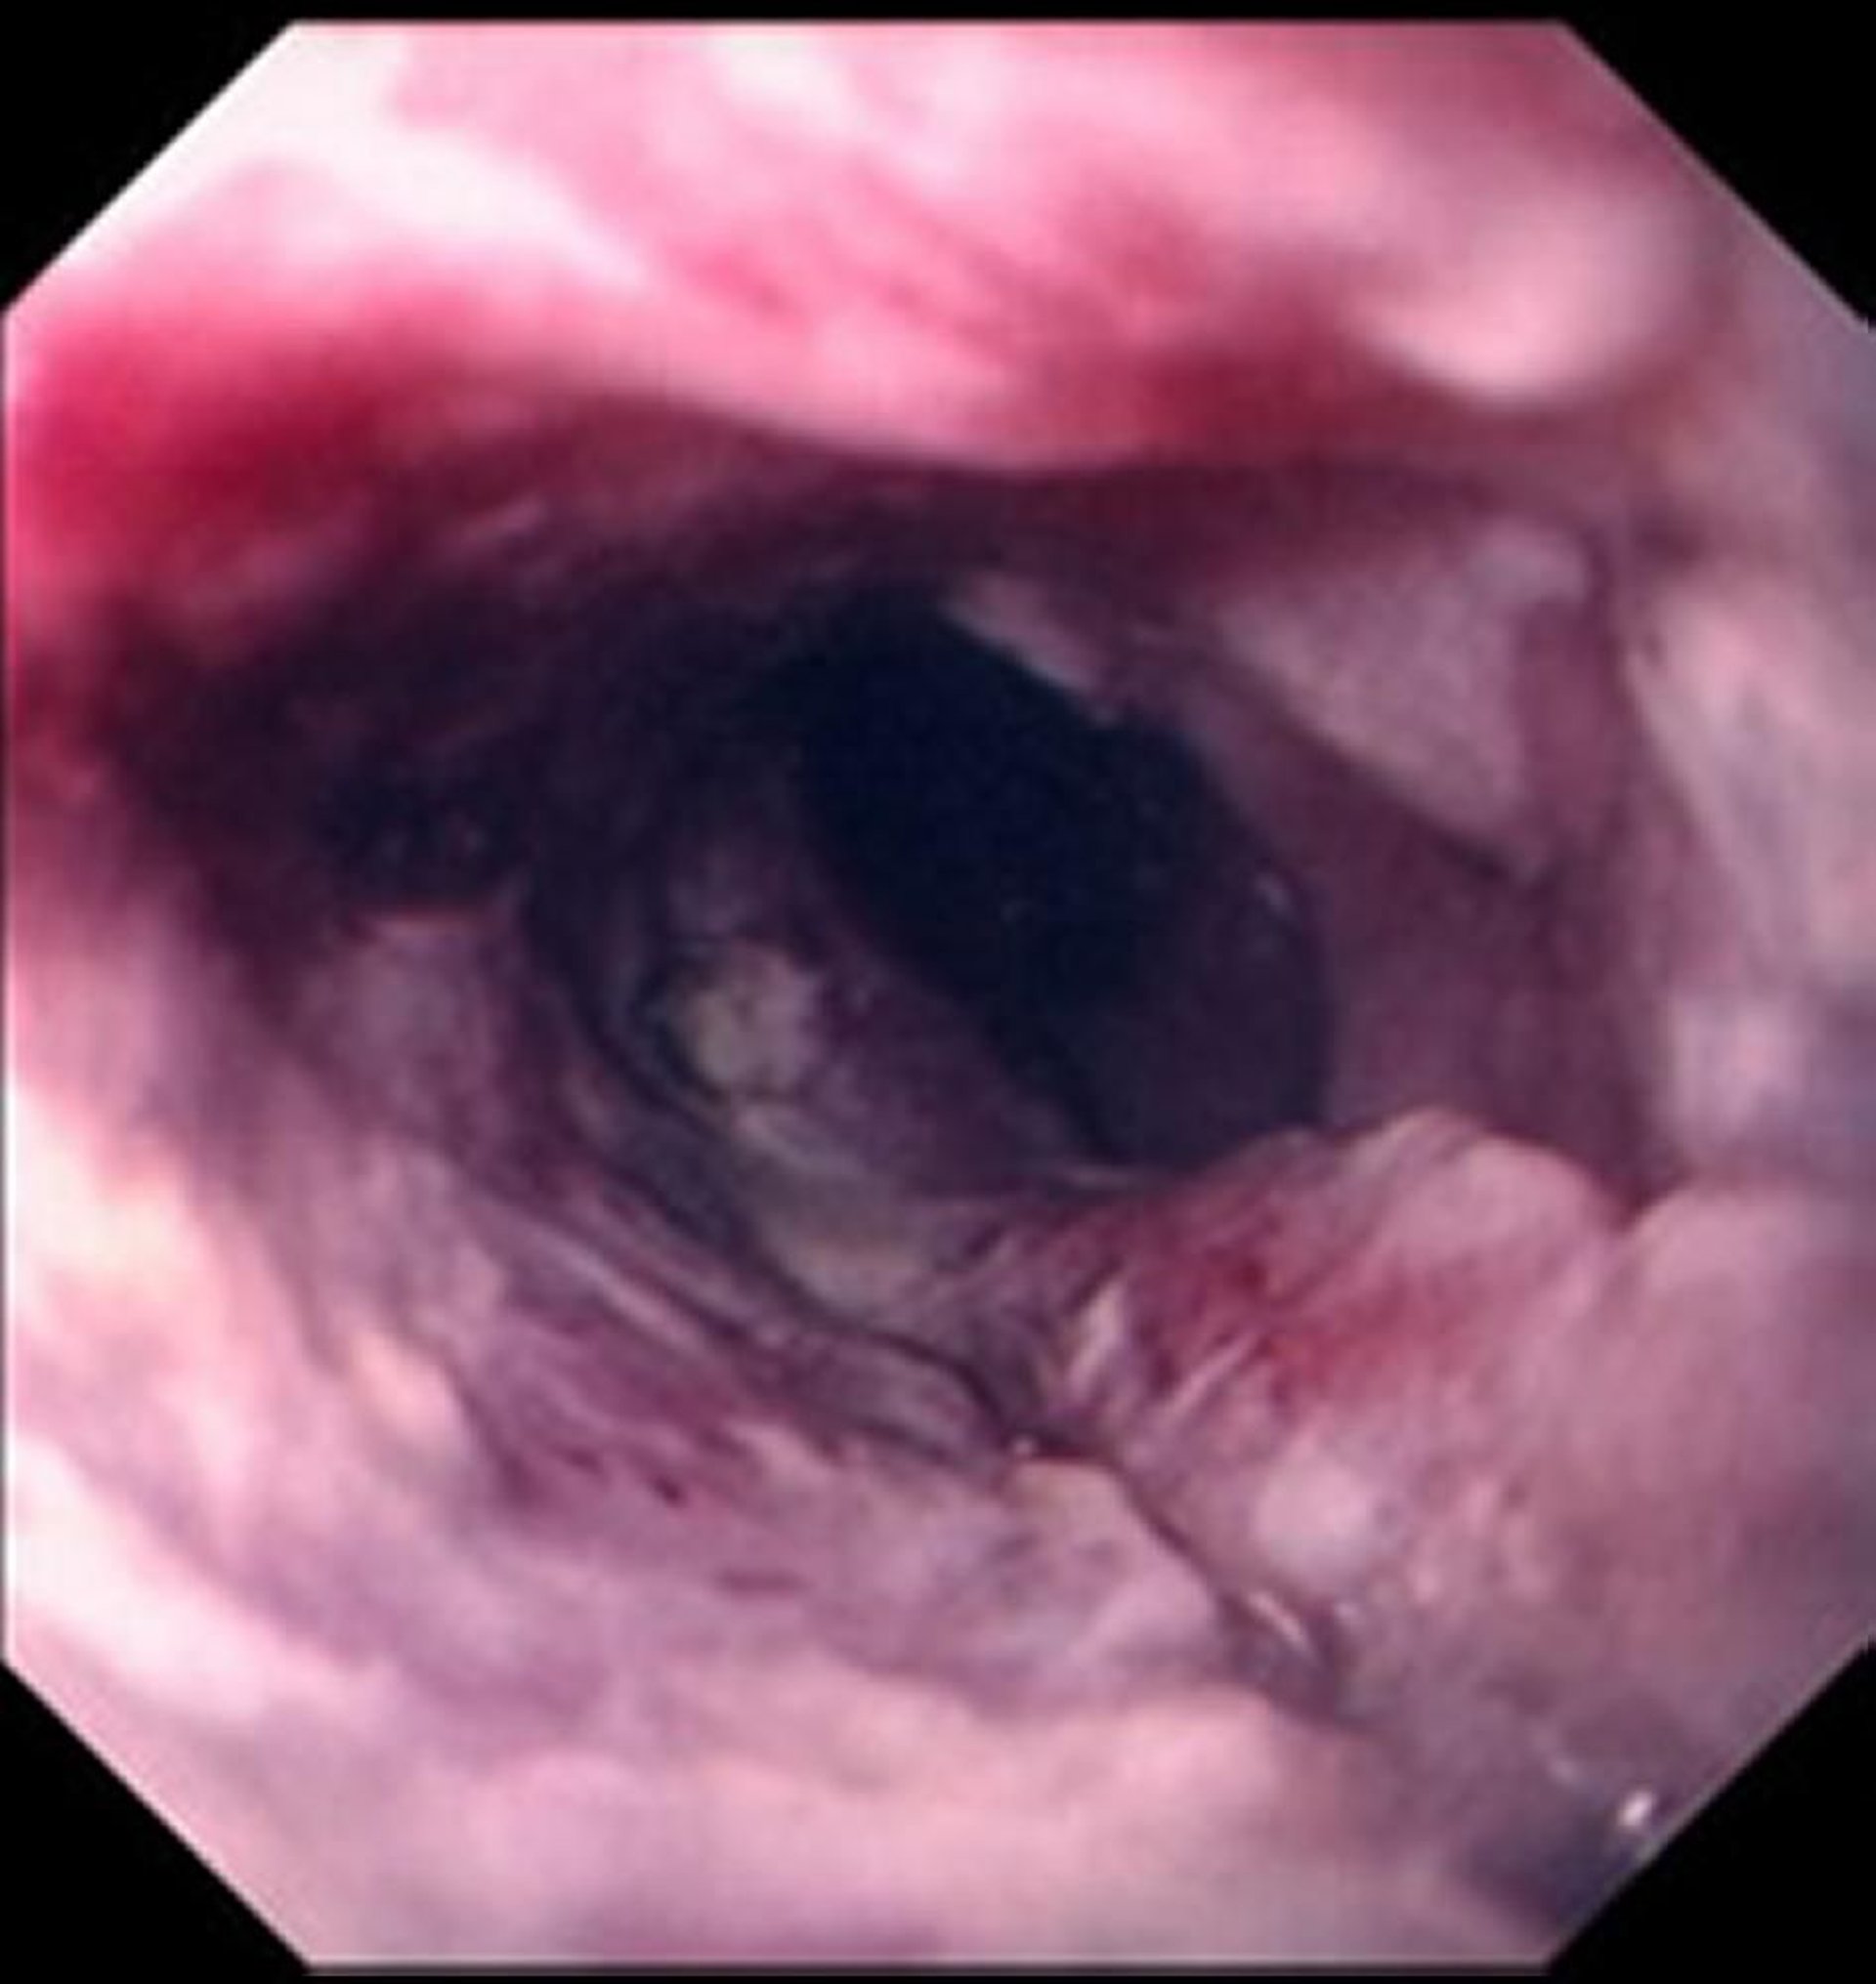

Carcinome malpighien de l'œsophage

Le carcinome épidermoïde se manifeste généralement par une masse ulcérée et déchiquetée qui réduit la lumière de l'œsophage.

Images provided by David M. Martin, MD.